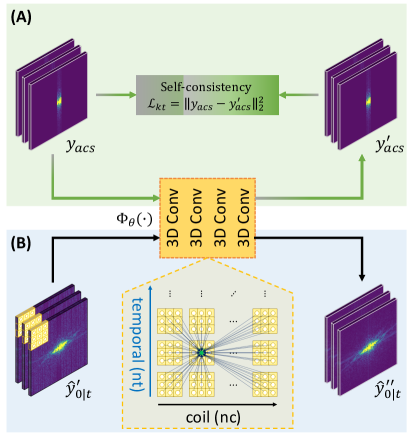

Inherited from the original DiMo method, the dDiMo framework features a forward diffusion process that introduces noise into k-space, followed by a reverse diffusion process that removes the noise to recover data. Unlike the original DiMo, which reconstructs static images, dDiMo incorporates additional temporal information from time-resolved dimensions, allowing it to capture dynamic features and enhance image reconstruction for dynamic MRI data. An illustrative diagram of the proposed dDiMo framework is presented in Figure 1. This new framework includes several key components designed to adapt to the reconstruction of dynamic image data: (1) A 3D CNN-based noise estimation network that characterizes spatial features within frames and temporal dynamics across frames, leveraging temporal coherence to learn denoising priors aware of temporal changes. (2) A 3D CNN-based - network that captures temporal dynamics in the spatiotemporal image domain from intermediate denoised results, guiding the diffusion process toward better temporal alignment. (3) A 3D CNN-based - network that enforces MRI physics constraints through data self-consistency learning within the ACS region of - space, refining the denoising process and ensuring consistency within k-space. (4) A nonlinear CG module that iteratively refines the reverse diffusion steps, maintaining adherence to physical constraints and enhancing robustness. Further details about each component will be provided in the following sections.

2.2.3 - priors for data self-consistency

Shift-invariant k-space correlations from fully-sampled auto-calibration signal (ACS) regions have been widely used for k-space interpolation and as regularization priors in MRI reconstruction [3, 22, 31]. In dynamic imaging, similar - patterns can be extracted from ACS data across consecutive time frames [49, 50]. Inspired by the work from scan-specific neural networks for k-space interpolation[22] and our previous k-space implementation [50, 31], we utilize a 3D CNN with four convolutional layers, each with a kernel size of 333, as shown in Figure 2, to capture - correlations through a self-consistency learning mechanism during the training phase. This process involves feeding ACS data from multiple time frames into the network, enabling it to learn the underlying - patterns by predicting the input data itself as accurately as possible, expressed mathematically as:

| (17) |

where denotes the 3D CNN that encodes the - priors from the ACS data, represents the ACS data used to capture the self-consistency - priors, and denotes the corresponding network prediction of . Once the training is complete, the learned priors can then be incorporated into the reverse diffusion to enforce the temporal frequency consistency of the k-space data recovery at each diffusion step. This process can be described as:

| (18) |

where is the result of Eq. (16). A schematic illustration of the use of - priors during training and inference is shown in Figure 2.